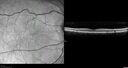

61 year old man with amelanotic choroidal nevus. Vision Normal - Stable over 4 years.

Amelanotic Choroidal Nevus - Multimodal Imaging577 views61 year old man with amelanotic choroidal nevus. Vision Normal - Stable over 4 years.00000